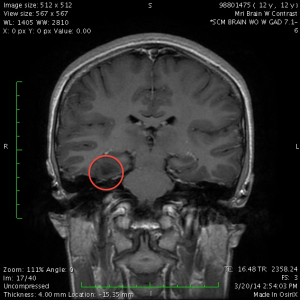

However, Dr. Cheshier’s manner made up for it. He patiently answered all of our questions, showed us the lesion on the MRI images, and talked about what the surgery would be like. He said that although the hippocampus was fairly close to the lesion, he was confident he would be able to resect the lesion without damaging the hippocampus. He said that this surgery had a 70% no-seizures-ever-again success rate, with another 20% chance of greatly reduced need for medication.

He ordered a follow-up MRI in 3 months, to verify that it was not growing.